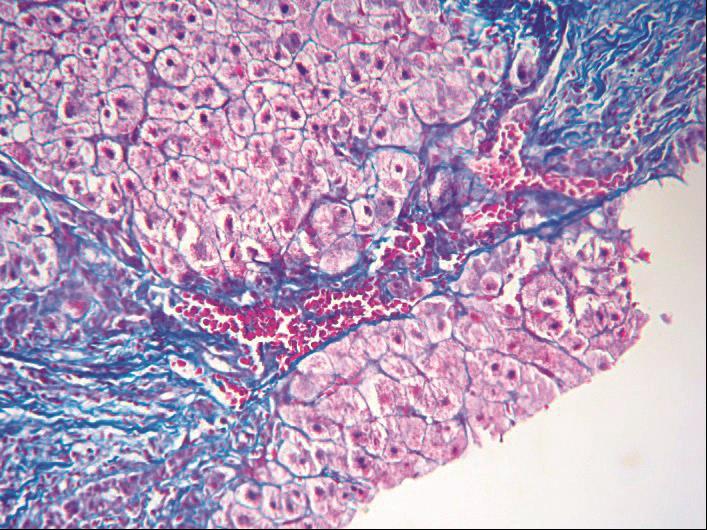

图4-3-5 酒精性肝病

肝Kupffer细胞活化,增生(免疫组化CD

68

)